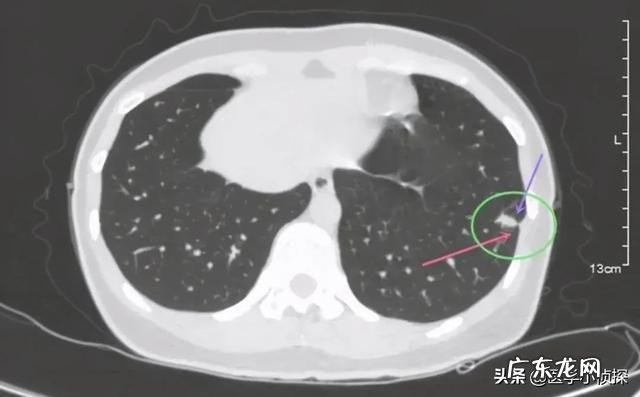

而且肺结节的话 , 它也不是我上面那张图那样的只有一种类型 。实际上 , 我们临床上发现的肺结节有很多种类型 , 比如说我们有下面这种只有实性成分的实性结节 。

文章插图